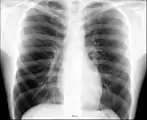

Anatomie radiographique d'une poitrine humaine. Anatomie radiographique d'une poitrine humaine.